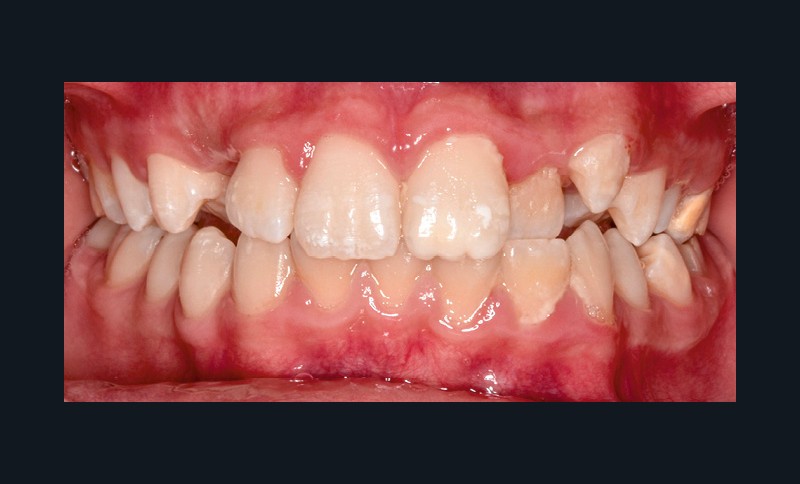

Sur le plan alvéolo-dentaire (fig. 1b) :

- Classe II subdivision gauche avec déviation du point inter-incisif mandibulaire à gauche ;

- occlusion inversée entre 22 et 32 ;

- dysharmonie dento-arcade (DDA) sévère ;

- 13 en position haute retenue.

Sur le plan squelettique : Classe II, schéma hypodivergent (fig. 1c). Sur le plan fonctionnel : aucune dysfonction ni parafonction.